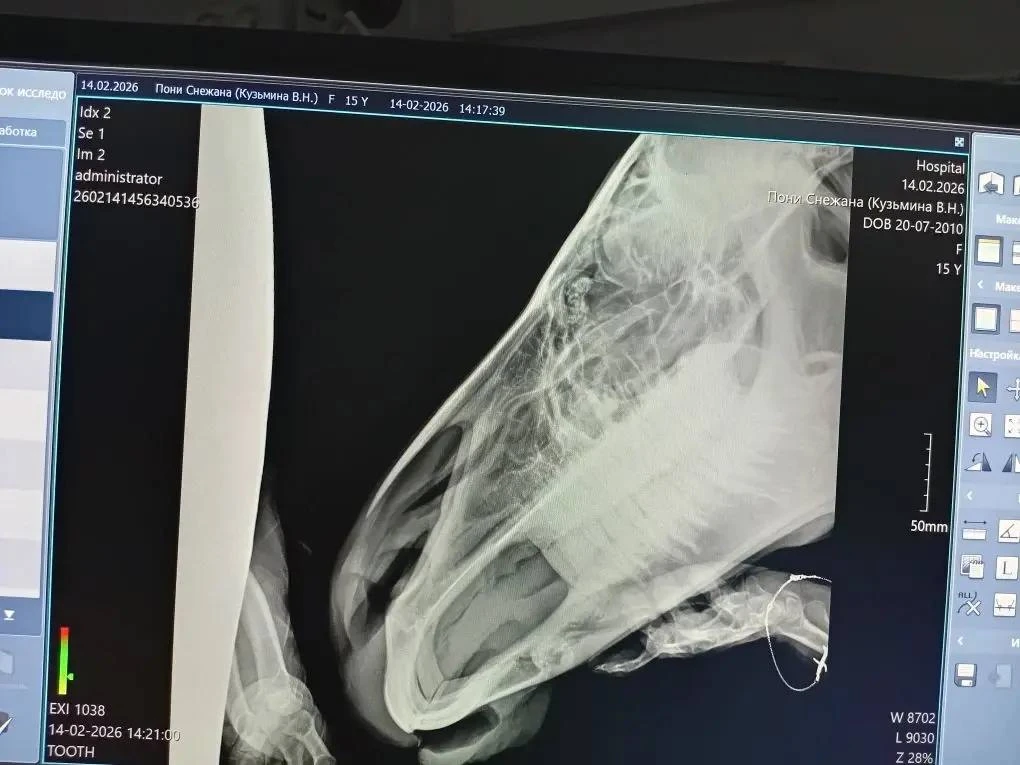

"Наши ветврачи предположили, что проблема может быть связана с патологией зубов и направили пони на рентген. Снежана стойко перенесла процедуру, хотя и оказалась в непривычной для себя обстановке в ветклинике для кошек и собак. Полученные снимки отправили в Красноярск для консультации с ветврачами, у которых больше опыта работы с животными на ипподроме", — рассказала начальник ветучреждения Марина Каримова.

Пони поставили диагноз "неодонтогенная киста верхней челюсти". Киста вытесняет здоровую костную ткань, делая ее тонкой и уязвимой. Возникает риск патологического перелома челюсти, нагноения. По словам ветврачей, для удаления кисты потребуется трепанация.